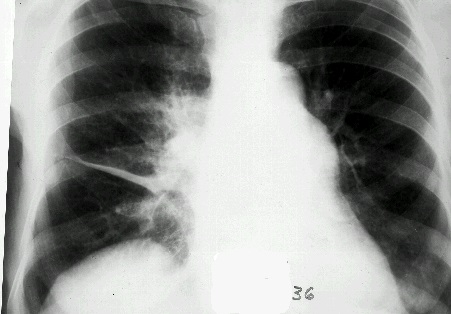

Плеврит может быть вызван большим количеством различных проблем. Первоначально, врач будет искать причину воспаления. Для этого он проведет обследование и выполнит рентгенографию грудной клетки. К возможным причинам плеврита могут относиться:

К другим причинам плеврита относится попадание воздуха в плевральную впадину из легких (пневмоторакс), грудные травмы (например, перелом ребра), туберкулез и другие инфекции.